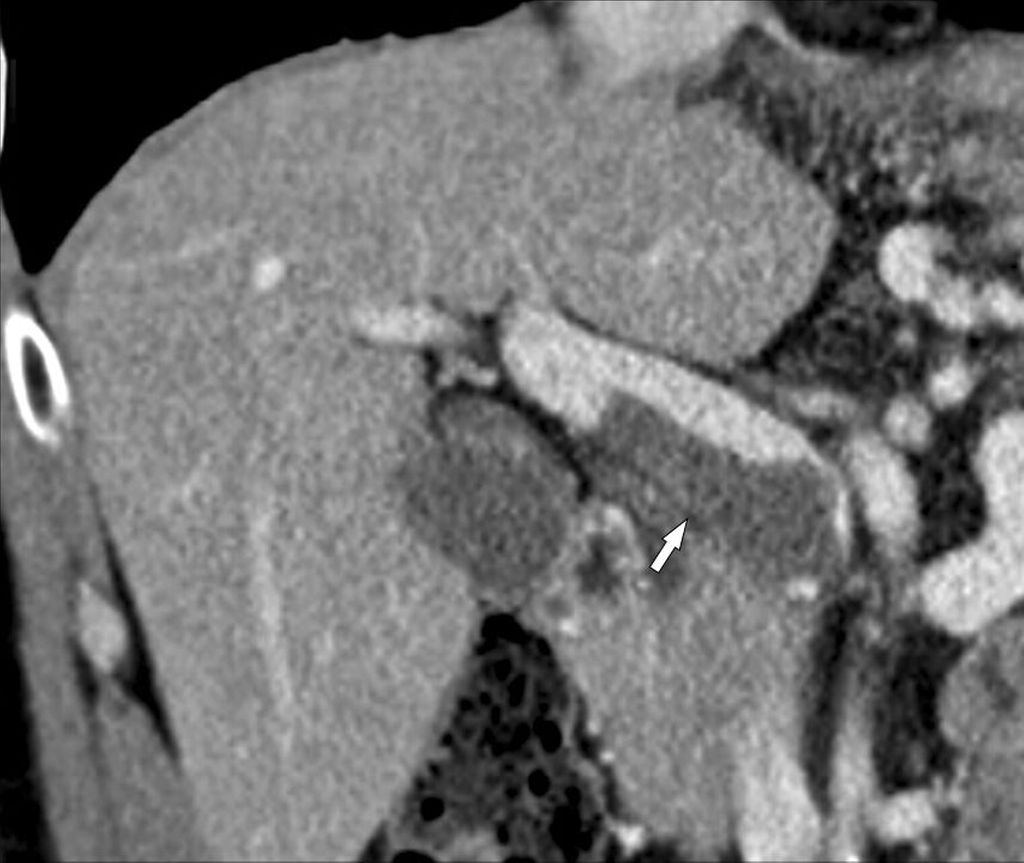

Die Häufigkeit eines hepatozellulären Karzinoms (HCC) ist wesentlich größer bei PVT-positiven als bei PVT-negativen Zirrhosepatienten (28,9% vs. 13,4%), was damit zusammenhängen mag, dass beide eher bei fortgeschrittener Zirrhose auftreten. Es ist essenziell, mittels Bildgebung nachzuweisen, dass der Pfortaderthrombus nicht mit dem HCC in Zusammenhang steht (Abb. 4). Ein HCC bei „blander“ Pfortaderthrombose ist in Abhängigkeit von Tumorstadium und Leberfunktion unter Umständen einer kurativen Behandlung (Resektion, interventionell-radiologische Tumorablation, Transplantation) zugänglich, während ein HCC mit „Tumorthrombus“ eine Kontraindikation für derartige Behandlungen darstellt.

Abb. 4: HCC und PVT: Das HCC im rechten Leberlappen (kleine Pfeile links) hat keinerlei Verbindung zum (blanden) Thrombus im Pfortaderhauptstamm, der kein Kontrastmittel aufnimmt (großer Pfeil)

Zirrhose und „HCC mit Tumorthrombus“

Abb. 5: HCC mit Tumoreinbruch in die Pfortader: Die MDCT (koronale 3D-Rekonstruktion) zeigt den Kontrastmittel-aufnehmenden Tumor, der vom rechten Leberlappen in den rechten Pfortaderast vorwächst und diesen massiv aufweitet (Pfeile)

Die Bezeichnung „HCC mit Tumorthrombus“ ist irreführend und sollte nicht mehr verwendet werden, da es hierbei zu einem direkten Vorwachsen des HCC in die Pfortaderäste (u.U. bis in den Hauptstamm) kommt und nicht zur Bildung eines Thrombus. In der MDCT oder der MRT ist dafür typisch, dass man ein kontinuierliches Vorwachsen des HCC aus dem Parenchym in die Pfortaderäste erkennt. Der intravasale Tumoranteil weitet die Pfortader aus und zeigt ein Kontrastmittelenhancement wie der Tumor (Abb. 5), während ein blander Thrombus typischerweise keine Kontrastmittelaufnahme aufweist (Abb. 5). Der intravasale Tumoranteil muss daher auch wie ein Tumor behandelt werden und nicht wie eine Thrombose. Das American College of Radiology hat deshalb in seiner LI-RADS®-Guideline für die Beurteilung von hepatalen Knoten in der Zirrhose die KategorieLI-RADS TIV („tumor in vein“) geschaffen, um diese besondere Tumorentität von den HCC mit oder ohne PVT klar abzugrenzen.